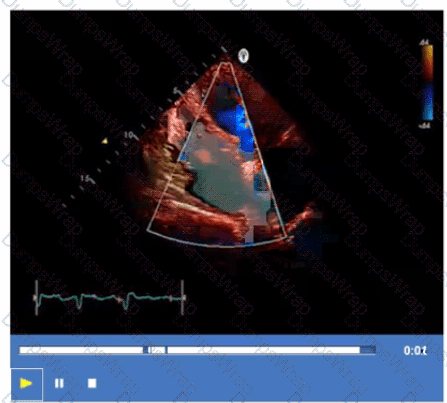

What is the incidental finding seen by color Doppler in this four-chamber view of a patient with left atrial enlargement?

CExplanation:

The color Doppler image in the four-chamber view shows a jet across the interatrial septum, indicating a shunt at the atrial level. In a patient with left atrial enlargement, the most common incidental finding causing such flow is a patent foramen ovale (PFO). A PFO is a small communication between the right and left atria that can open under certain pressure conditions, leading to shunting.

Muscular ventricular septal defect is a ventricular level defect and would be seen in different views. Coronary-cameral fistula is a rare anomaly involving abnormal connections between coronary arteries and cardiac chambers, not typical in this setting. Sinus venosus defect is an atypical atrial septal defect located near the superior vena cava and would require different imaging planes for detection.

This finding and its implications are discussed in the "Textbook of Clinical Echocardiography, 6e", Chapter on Atrial Septal Defects and Shunts【20:115-120†Textbook of Clinical Echocardiography】.